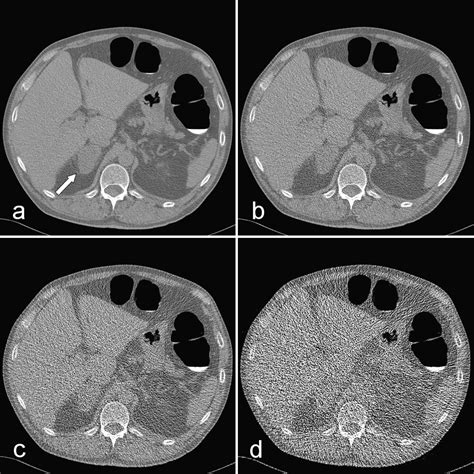

At its core, Ct Scan Colonography is a specialized radiological imaging test that produces 2D and 3D images of the large intestine. Unlike a standard colonoscopy, which involves physical exploration of the bowel, this procedure relies on computed tomography (CT) to create a detailed internal map. The process requires the patient’s colon to be inflated with air or carbon dioxide to ensure the walls of the bowel are fully distended, which allows the CT scanner to capture clear, unobstructed views of the lining.

• Imaging: The patient will hold their breath for brief intervals while the scanner captures high-resolution images, usually in two positions: once while lying on their back and once while lying on their stomach (or side).